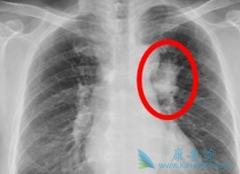

据目前统计到的数据显示,肺癌的5年生存率在美国为15%,欧洲为10%,发展中国家包括我国大概是8.9%。分子靶向药物特罗凯( 厄洛替尼 )的出现彻底改变了肺癌患者的预后。所以,医学界就把肺癌治疗的希望寄托在靶向治疗上。特罗凯(厄洛替尼)以肿瘤细胞膜 ...

肺癌是我国常见的恶性肿瘤之一。肺癌主要分 小细胞肺癌 (SCLC)和非小细胞肺癌(NSCLC)。小细胞肺癌(SCLC)约占肺癌的15%,尽管近年来其发病率相对较低,但大部分SCLC患者发现时已处于广泛期,导致总体生存率偏低,且具有恶性度高、侵袭性强、进展较快 ...